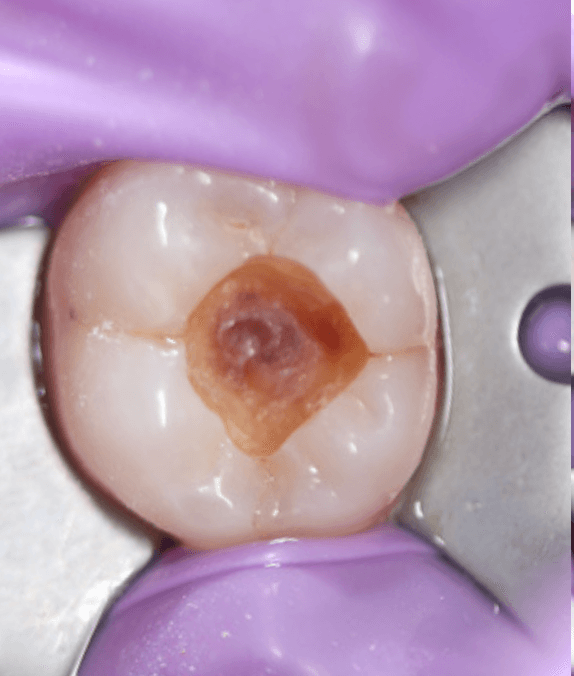

We have a hole